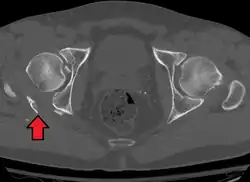

Axial CT image (viewed on bone windows) of a complex comminuted left acetabular fracture involving both anterior and posterior columns. -

Fracture of the acetabulum